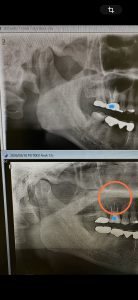

③

浅草橋時代からの方、インプラント2本併用に下手前6番分岐は再生治療

④

これも根管治療で治る、開かないMB1は根切併用かな

良くなりますよ!